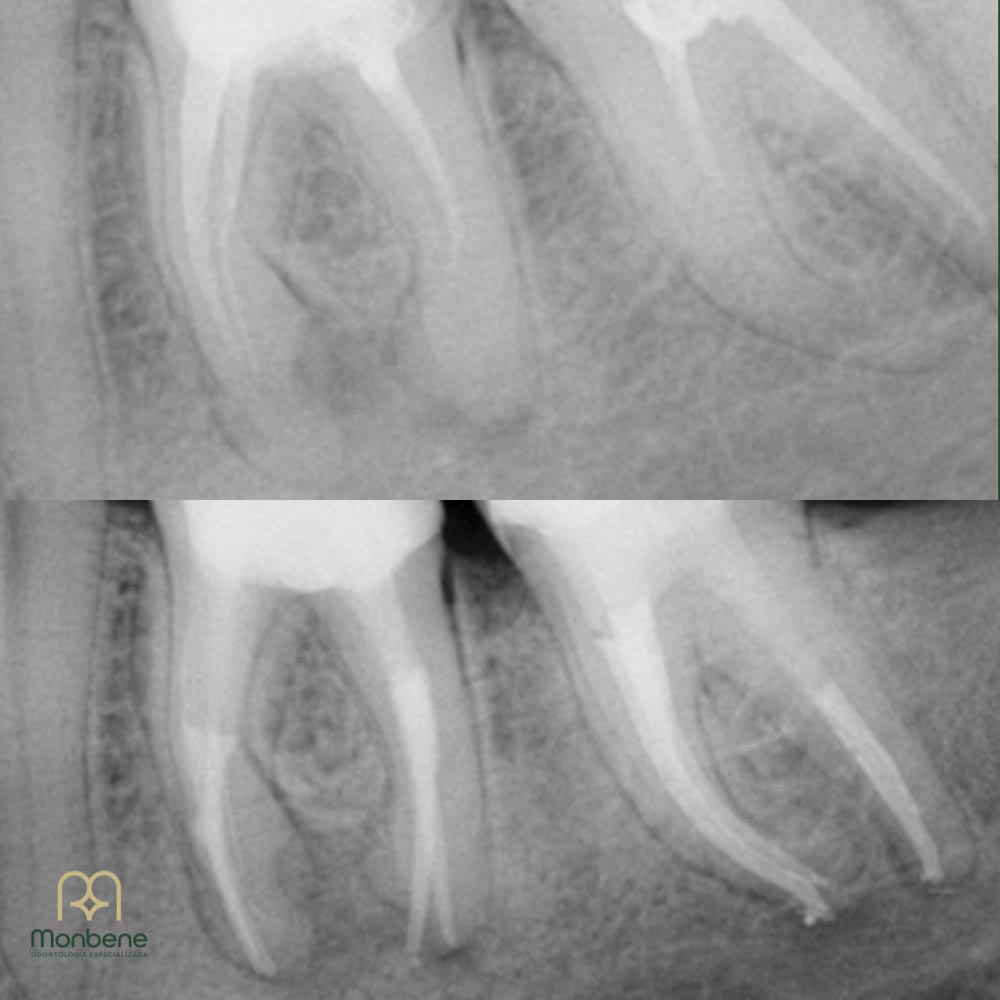

A endodontia é a especialidade da odontologia responsável pelo tratamento do canal do dente. Ela atua quando a polpa dental — a parte interna onde ficam nervos e vasos sanguíneos — sofre inflamação ou infecção, geralmente causada por cárie profunda, fratura ou trauma. O objetivo é preservar o dente, eliminando a dor e devolvendo sua função.

O uso do microscópio odontológico trouxe mais precisão e segurança ao tratamento de canal.

Mais precisão

garantindo limpeza completa e reduzindo riscos de falhas;